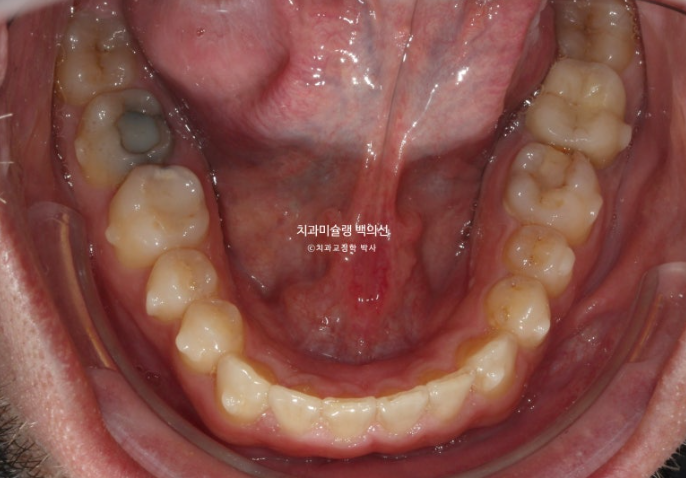

MTA 부분교정용 장치를 붙인 직후 환자분은 세달간 긴 여름 휴가를 보내기 위해 본국으로 갔고 25년 9월 다시 한국에 돌아왔습니다.

앞니 치축 개선을 확인 한 후 드디어 치료를 종료 합니다.

25.09

치아 뿌리 평행도는 사랑니까지 좋습니다.

중심선은 잘 맞고 과개교합은 깔끔하게 개선이 되었습니다.

어금니 교합은 물샐틈 없이 좋고 1급 교합관계를 보입니다.